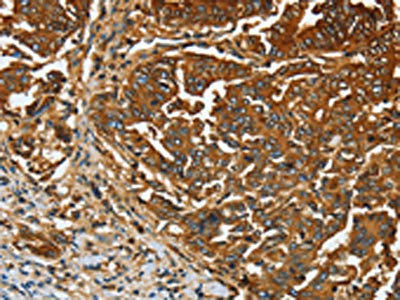

The image on the left is immunohistochemistry of paraffin-embedded Human gastic cancer tissue using CSB-PA160116(CEACAM5 Antibody) at dilution 1/20, on the right is treated with fusion protein. (Original magnification: ×200)